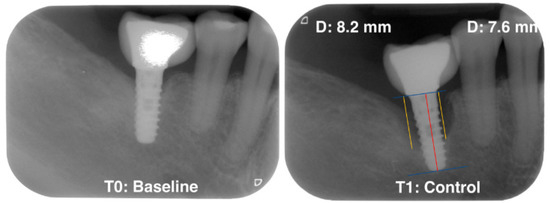

Standardized radiographs should be taken and compared with baseline radiographs when implants were placed in function [8]. The peri-implant radiographic bone loss (MBL) was determined by a calibrated examiner (VA) who calculated the possible bone loss by taking linear measurements from the most mesial and distal part of the implant platform to the crest bone in each implant. (Figure 1).

Figure 1.

Measurement of radiographic bone loss.